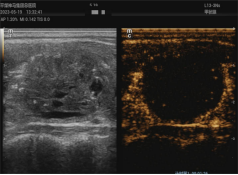

1、超聲引導(dǎo)下腫瘤的熱消融治療

熱消融技術(shù)是指在超聲實(shí)時(shí)引導(dǎo)下,將消融針插入病灶內(nèi),產(chǎn)生的高溫在短時(shí)間內(nèi)使病灶組織凝固壞死的方法。這一方法操作微創(chuàng)精準(zhǔn),效率高,范圍可控,不良反應(yīng)小,可重復(fù)性強(qiáng),實(shí)現(xiàn)了治療的微創(chuàng)、美觀、有效、安全的完美結(jié)合??剖议_展甲狀腺、乳腺、肝臟、子宮、淋巴結(jié)等多臟器實(shí)體腫瘤的熱消融治療多年,積累了豐富的臨床診治經(jīng)驗(yàn),患者受益,提高了患者的生活質(zhì)量。